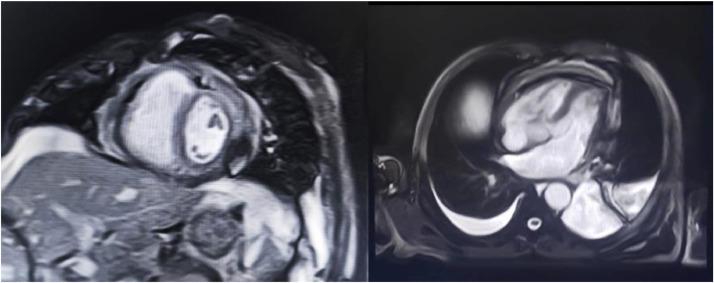

Chronic constrictive pericarditis is a pericardial affection that causes a severe impairment of myocardial compliance. Among its many etiologies, tuberculosis is the most common cause, mainly in developing countries. Multimodal imaging methods are essential tools for guiding diagnosis. We present the case of a 64-year-old man with no past medical history who presented with dyspnea stage II of NYHA and right heart failure. At admission, he was stable, with normal blood pressure and a normal heart rate. His ECG showed a low voltage of QRS complexes. Transthoracic echocardiography revealed significant pericardial thickening enveloping the ventricles, with significant respiratory flow variation. A thoracic CT scan and cardiac MRI confirmed the presence of pericardial thickening and calcifications. The patient underwent beat-heart pericardial decortication. The anatomopathological examination of the surgical piece revealed Mycobacterium tuberculosis. The postoperative check-up after 6 months showed good clinical and echocardiographic evolution.

慢性缩窄性心包炎是一种导致心肌顺应性严重受损的心包疾病。在其众多病因中,结核病是最常见的病因,主要发生在发展中国家。多模态成像方法是指导诊断的重要工具。我们报告一例64岁男性患者,既往无病史,出现纽约心脏协会(NYHA)II级呼吸困难和右心衰竭。入院时,他病情稳定,血压正常,心率正常。他的心电图显示QRS波群低电压。经胸超声心动图显示心室周围心包显著增厚,伴有显著的呼吸血流变化。胸部CT扫描和心脏磁共振成像证实存在心包增厚和钙化。患者接受了心脏不停跳心包剥脱术。手术标本的解剖病理学检查发现结核分枝杆菌。6个月后的术后检查显示临床和超声心动图有良好的进展。